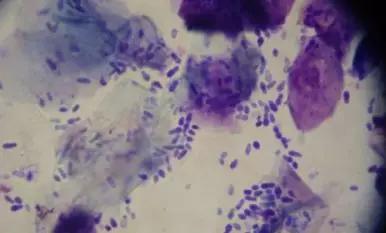

马拉色菌在每个人的头皮上都有,位于皮脂腺分布的部位,正常时与人类和平共存,以头皮上分泌的油脂(皮脂)为食物,而头皮无时无刻都在产生油脂,下图就是马拉色菌。